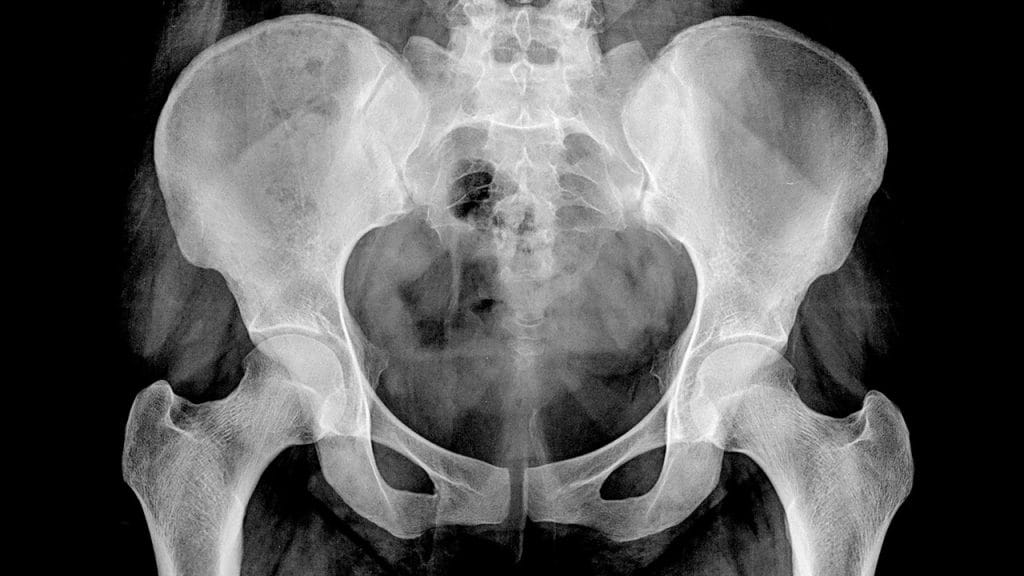

Fast. Simple. Essential. X-rays are one of the most widely used diagnostic tools, providing clear, detailed images of bones, joints, and internal organs. Whether you need to check for a fracture, assess a lung condition, or investigate persistent pain, an X-ray can offer quick answers, guiding the next steps in your care.

An X-ray is a quick and painless imaging test that uses a small dose of radiation to capture images of the inside of your body. It’s especially effective for examining bones and joints, but it’s also used to assess the lungs, heart, and abdomen.

- Dense structures, like bones, appear white on the image.

- Softer tissues appear in varying shades of grey, providing a clear picture of the area being examined.

✔ Bone fractures – Clear images show the extent of a break or injury.

✔ Joint dislocations & arthritis – Helps diagnose joint problems, including dislocations or wear and tear due to arthritis.